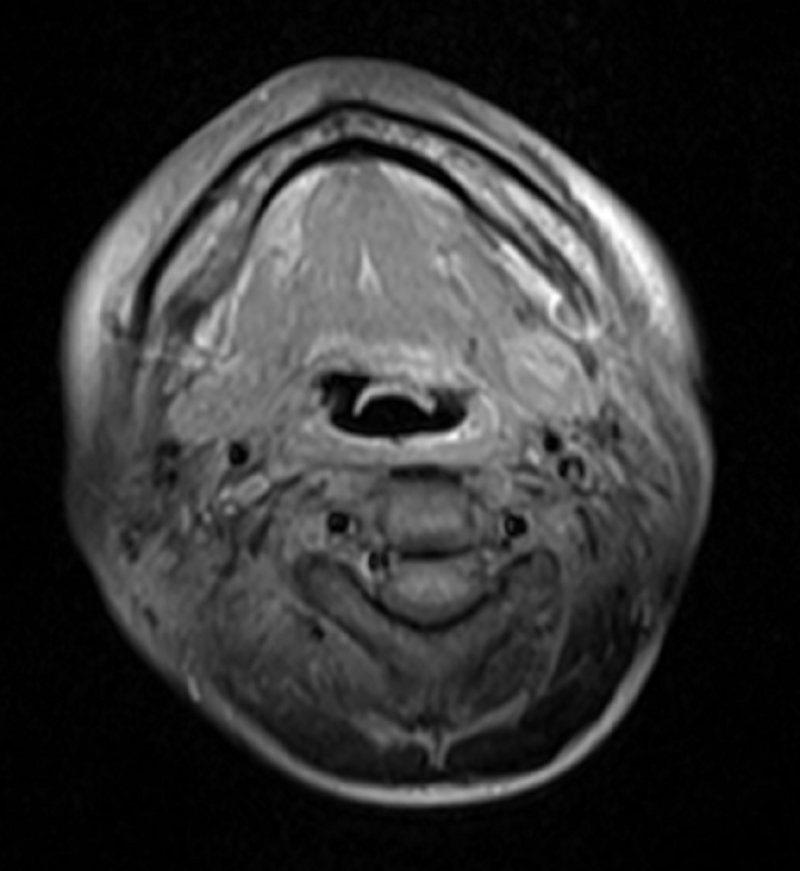

自2020年7月小萍确诊鼻咽癌并颈部淋巴结转移后至肿瘤科二区就诊至今,生存期已达3年时间,且极大地改善了生活质量。2023年6月,小萍复查肿瘤消退无复发,病情稳定。

2022年8月2日射波刀治疗后,肿瘤已消退